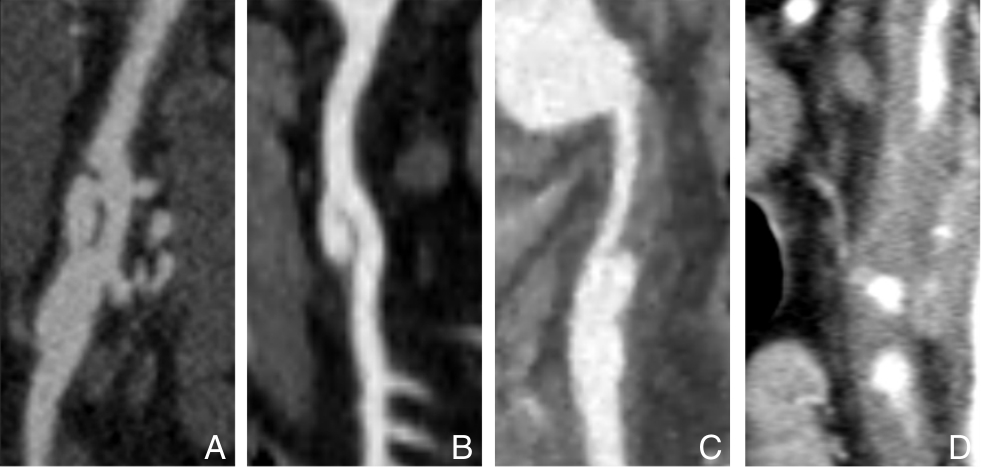

摘要:背景与目的 自发性孤立性肠系膜上动脉夹层(SISMAD)是一种较为常见的内脏动脉夹层疾病,主要表现为急性腹痛,严重者可引发肠缺血甚至坏死。随着CT血管成像(CTA)等影像技术的普及,SISMAD的检出率显著提高,但目前针对其治疗策略仍存在争议,尤其在保守治疗与腔内介入治疗之间的选择缺乏统一标准。为探讨两种治疗方式的临床效果及适应人群,本研究回顾性分析本中心SISMAD患者的临床资料,并比较不同治疗方式的短中期疗效,为制定个体化治疗策略提供依据。方法 回顾性分析2018年1月—2023年12月浙江省宁波市第二医院确诊的174例SISMAD患者临床资料,其中保守治疗30例,腔内介入治疗144例(包括支架植入和部分假腔弹簧圈栓塞联合支架植入)。术前均行CTA或肠系膜上动脉造影并分型。随访评估患者术后1个月和1年症状缓解情况及影像学指标,包括夹层重塑率、支架通畅性等。结果 保守治疗组1个月症状缓解率为90.0%,1年为92.8%;介入治疗组分别为99.3%和98.6%。1个月症状缓解率差异具有统计学意义(P=0.016),1年症状缓解率差异无统计学意义(P>0.05)。分型亚组比较中,介入治疗组各型症状缓解率普遍高于保守治疗,但差异均无统计学意义(均P>0.05);保守治疗组Ⅲ型患者症状控制较差,出现死亡病例。介入治疗成功率为99.3%,1年内支架移位或闭塞为0例,完全重塑率为86.8%,支架通畅率为100%。部分患者支架内出现少量附壁血栓,未见血流阻断。结论 腔内介入治疗对SISMAD患者具有较高的技术成功率和良好的短中期疗效,尤其适用于真腔血流受限的Ⅱ型及Ⅲ型患者。建议根据夹层分型及血流受限程度,个体化制定治疗方案,以提升疗效、降低风险。